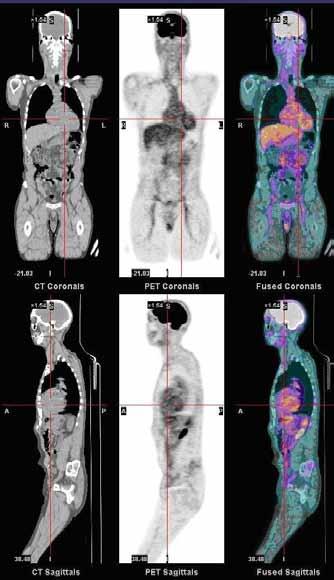

35 Introduction to Nuclear Medicine by Dr. Bennett S. Greenspan

Dr. Ben Greenspan, M.D. (U.S.), Board of Directors, the American Board of Science in Nuclear Medicine; Past President, Society of Nuclear Medicine and Molecular Imaging